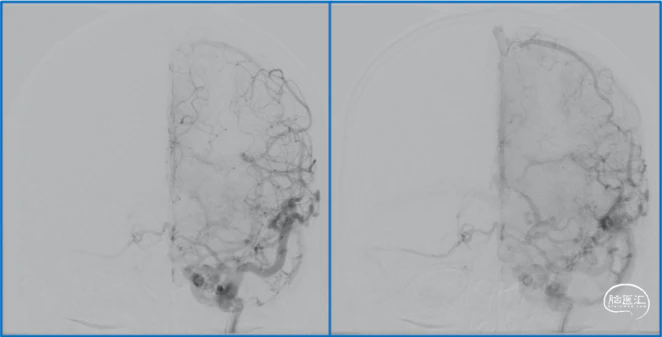

典型病例

蝶顶窦旁DAVF属于Borden III型,需要积极外科治疗。

蝶顶窦旁DAVF,可吸引前和中颅窝硬膜的所有动脉参与供血。其中颈内动脉及其分支的供血可以使用显微外科技术阻断;颈外动脉的供血动脉可以使用介入栓塞技术阻断。

介入栓塞眼动脉供血的要点:超选左侧眼动脉,跃过视网膜中央动脉,栓塞脑膜回返动脉对DAVF的供血。目的:保护眼动脉视网膜中央动脉分支,避免后期栓塞颈外动脉的供血动脉时损伤眼动脉。

引流静脉是否引流进入海绵窦,决定DAVF诊断为“颈动脉-海绵窦动静脉瘘”还是“蝶顶窦旁DAVF”。

静脉的引流路径决定患者静脉高压的临床表现,预后风险,治疗方案。

稳妥的外科治疗方案:先介入栓塞颈外动脉的供血动脉,然后显微手术切断颈内动脉的供血动脉,阻断引流静脉,电凝封闭硬膜瘘口。

神经内镜可以辅助确认颞极深部的引流静脉,避免残留引流静脉。